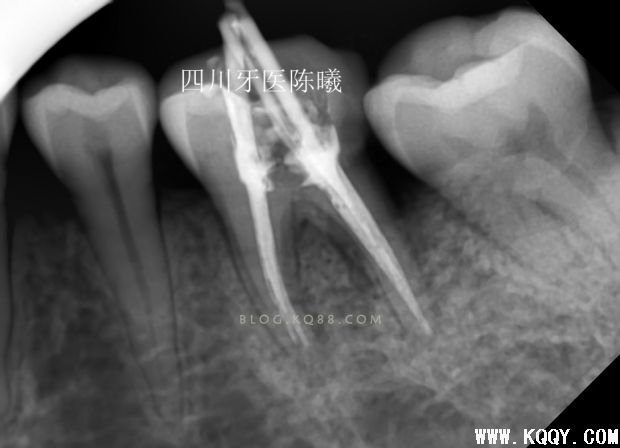

这次留个后路,把刚才超填的牙胶去掉头部1MM,然后保留大部分牙胶,紧密充填后拍片!,终于感觉及格了,还是多角度看看

进一步确定感觉没有大问题了,终于可以告诉患者根充结束了,由于反复操作,时间过长,担心出问题,病人也在考虑要不要做修复体,所以最后暂封上部观察